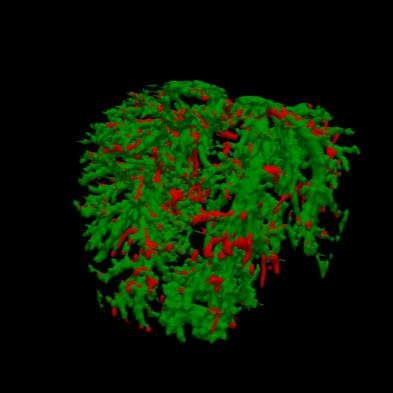

Manually segmenting the hepatic vessels from Computer Tomography (CT) is far more expertise-demanding and laborious than other structures due to the low-contrast and complex morphology of vessels, resulting in the extreme lack of high-quality labeled data. Without sufficient high-quality annotations, the usual data-driven learning-based approaches struggle with deficient training. On the other hand, directly introducing additional data with low-quality annotations may confuse the network, leading to undesirable performance degradation. To address this issue, we propose a novel mean-teacher-assisted confident learning framework to robustly exploit the noisy labeled data for the challenging hepatic vessel segmentation task. Specifically, with the adapted confident learning assisted by a third party, i.e., the weight-averaged teacher model, the noisy labels in the additional low-quality dataset can be transformed from "encumbrance" to "treasure" via progressive pixel-wise soft-correction, thus providing productive guidance. Extensive experiments using two public datasets demonstrate the superiority of the proposed framework as well as the effectiveness of each component.